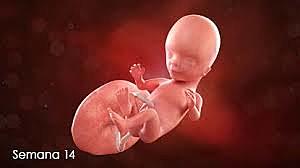

• Semana 14

Semana 14

las orejas del feto se encuentran implantadas a ambos lados de la cabeza y también los ojos se han acercado, ya se distingue el puente de la nariz. El cuello se ha alargado y el mentón ya no descansa sobre el pecho.